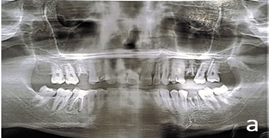

Although chairside examination was restricted, the patient permitted an OPG radiograph shown in Figure 1a , which revealed pathology involving all four first molars. Findings included:

- #16 – Fractured crown with pain and sensitivity.

- #14 – Deep Caries

- #15, #11, #12 – Proximal Caries

- #26, #36 – Root piece (Figure 2a and 2b)

- #46 – Root canal treated tooth with chronic periapical pathology

Figure 1a: Before treatment OPG